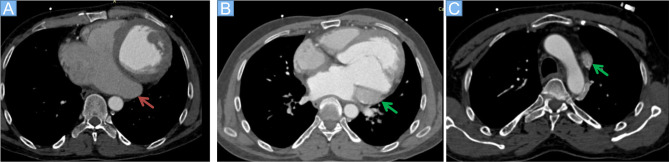

Case presentation: We report the case of a 45-year-old male who presented with progressive symptoms of heart failure, including dyspnea, fatigue, and reduced exercise tolerance. Initial workup revealed an unexplained dilated coronary sinus and reduced left ventricular function with dilated heart chambers. Further imaging with contrast-enhanced echocardiography and CT angiography confirmed the presence of a PLSVC draining into the coronary sinus with absence of right superior vena cava. No other congenital heart defects were identified like coronary sinus atrial septal defect (ASD). The delayed diagnosis of PLSVC likely contributed to chronic atrial stretch, arrhythmia development- atrial fibrillation in this case, and eventual heart failure symptoms.